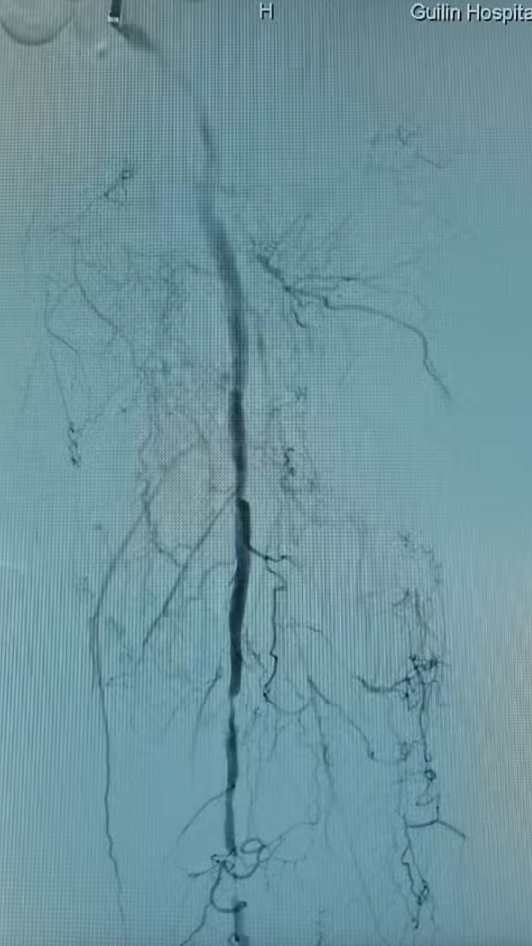

股浅动脉长段闭塞段术前(左)血流中断,术后(右)真腔成功开通

在激光成功“开路”后,团队再辅以必要的球囊扩张,最终实现血管的完美重建。术后复查显示,患者下肢血流恢复通畅、疼痛消失,保肢成功,生活质量得到根本性改善。